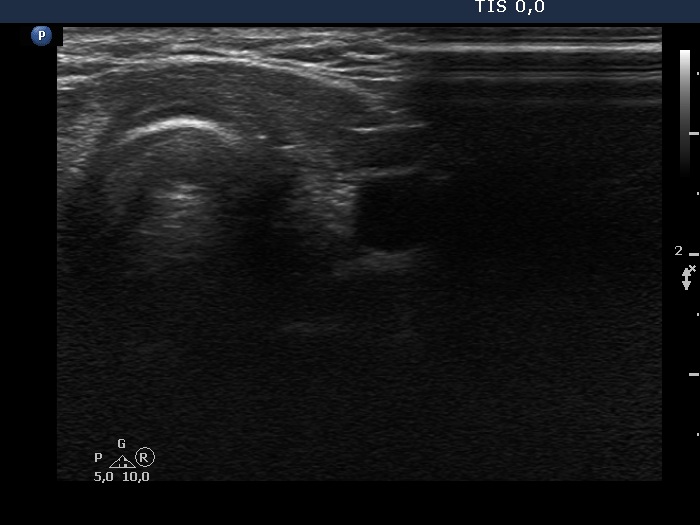

Ultrasonography revealed that the discrete hypoechoic lesion in the left lobe had increased in size, the dimensions were 4x4x5 mm, width, depth and length, respectively. There was a lymph node lateral to the left lobe. The node presented a heterogeneous pattern and lacked a regular hilum.Suggestion: repeat ultrasound in 3 to 6 months.

The small hypoechoic lesion within the left thyroid corresponds to a remnant. It seems to be realistic that this is thyroid tissue, but we have no particular reason to assume it would be a malignant lesion.

However, the lymph node is suspicious, especially due to its heterogeneity.